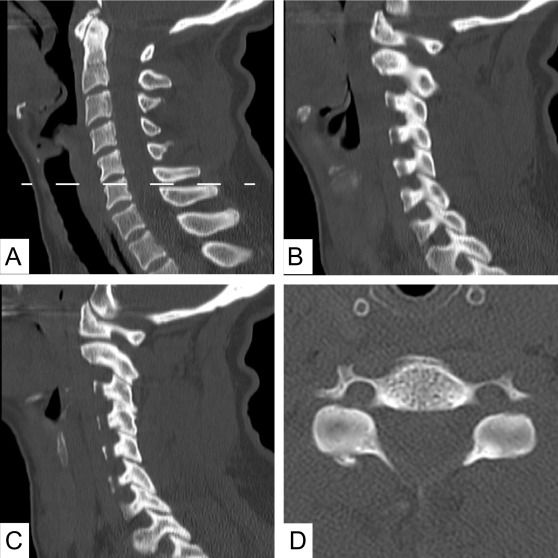

Pemeriksaan CT scan merupakan suatu pemeriksaan pencitraan yang bersifat non-invasif, yang menggabungkan foto sinar-X dan teknologi komputer untuk menghasilkan gambaran tubuh dalam berbagai aksis (horizontal atau aksial).

Pemeriksaan CT scan dapat menunjukkan gambaran detail bagian tubuh yang diperiksa, misalnya tulang, otot, lemak, dan organ-organ tubuh. Hasil pemeriksaan CT scan lebih detail dibandingkan foto rontgen sinar-X biasa.

Pada CT scan, sinar-X dipancarkan melingkari bagian tubuh yang diperiksa, sehingga menghasilkan gambaran dari berbagai sisi dari organ atau struktur yang sama. Informasi gambaran yang dihasilkan kemudian dikirim ke komputer untuk menginterpretasi data yang didapat dan ditampilkan ke monitor.

CT scan tulang belakang merupakan pemeriksaan CT scan yang dilakukan untuk mendapatkan informasi yang lebih detail tentang tulang belakang dan struktur lain di sekitarnya dibandingkan dengan foto rontgen biasa.